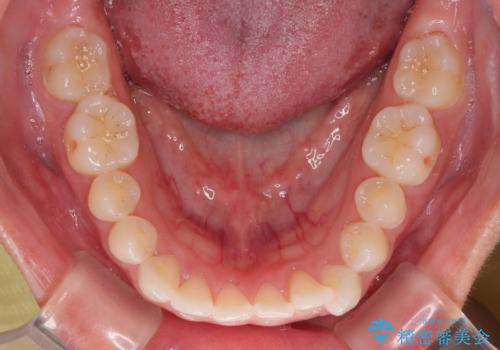

- 上下前歯のデコボコを気にして来院された患者様です。

ワイヤー矯正でもマウスピース矯正でも可能でしたが、短期間で、自身の手を煩わせることなく治療を行いたいとのことで、ワイヤー装置にて矯正治療を行うこととしました。